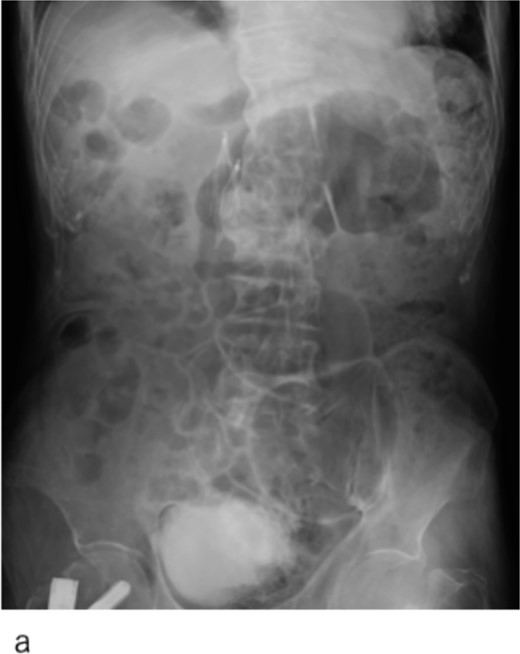

After confirming the absence of progressive anemia because of the hemorrhage from the femoral fracture, heparin was administered systemically. Following improved arterial blood oxygenation, NPPV was discontinued on hospital Day 3, and oxygen administration was discontinued on hospital Day 10. The patient was discharged on Day 15 of hospitalization. Enhanced computed tomography revealed that the IVCF did not move (Fig. 4a–c) and the pulmonary embolism improved; however, the thrombus remained in the left femoral and popliteal veins.

Computed tomography images 14 days after surgery. (a,b) The IVCF is still folded and not open. (c) Legs of IVCF are still folded.

IVCF is generally considered safe, with a low incidence of acute complications. In addition, instances of IVCF opening failure are very rare. Ganesh et al. reported that IVCF ‘failed to open’ only in 27 (0.18%) out of 14 784 cases [2]. The etiology of IVCF opening failure has been attributed to entanglement of the IVCF legs [3], misplacement into the gonadal or femoral veins [3, 4], or thrombus formation in the delivery sheath during deployment [5, 6]. In our case, the etiology was assumed to be entanglement of the IVCF legs or misplacement of the IVCF tip into the left gonadal vein based on the shape of the failed ICVF (Figs 2a and 4c).

Despite being effective in avoiding the migration of the unopened IVCF and treatment of the acute pulmonary thromboembolism, our approach remained of concern. IVCFs have been reported to cause chronic perforation to the IVC wall, even with appropriate deployment [9]. In this patient, the tip of the unopened IVCF was folded (Figs 3 and 4c); thus, the risk of perforation increased because of the stiffness of the folded IVCF legs. Therefore, close monitoring is required.